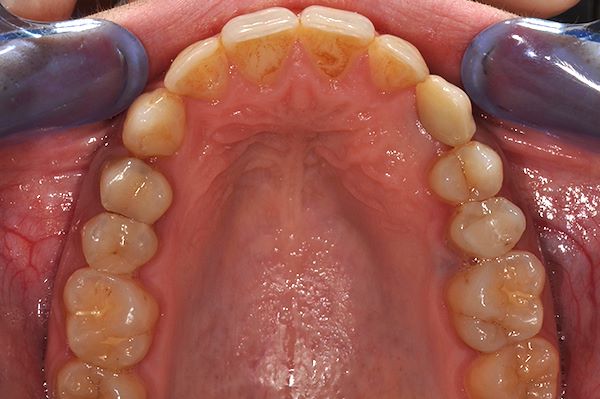

Paziente 28 anni con morso profondo e affollamento inferiore importante, canino superiore di sn (2.3) incluso con presenza del canino da latte. Il piano di trattamento ha previsto il trattamento ortodontico multibrackets con estrazione del canino incluso, estrazione del canino da latte e posizionamento dell’impianto in sede del canino mancante. A rimozione dell’apparecchiatura è stato posizionato un provvisorio per condizionare i tessuti molli.